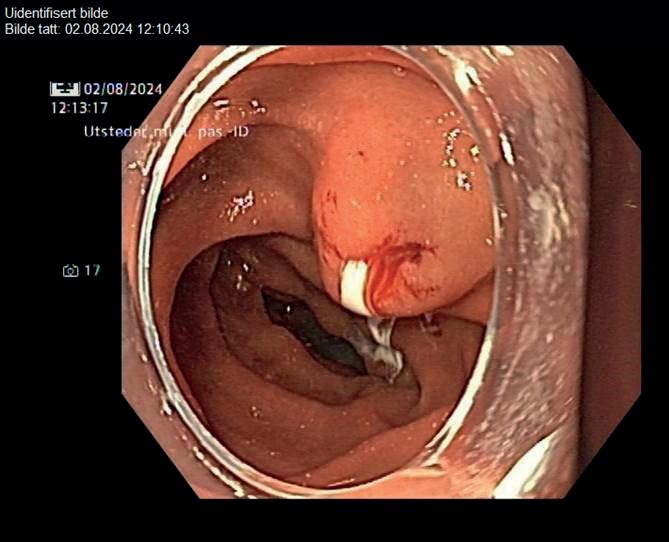

46 Bildequiz